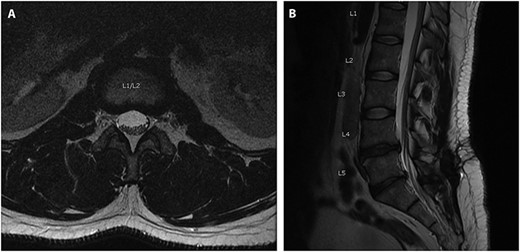

A 34-year-old male who was admitted for revision L5-S1 and primary L4-L5 decompression and posterolateral instrumented fusion of L4-S1. Eight months prior he had undergone a left sided laminectomy and discectomy of L5-S1 for disk herniation. A few months after his initial fusion procedure, the patient reported falling down a flight of stairs and developed worsening lower extremity pain and radicular symptom. Preoperative imaging 3 months prior to his revision showed recurrent disk herniation at L5-S1 as well as new herniation at L4-L5 (Fig. 1). The procedure went without complication, with no note of durotomy, and the fascia was closed using a bidirectional barbed suture.

Axial (A) and Sagittal (B) T2 MRI imaging obtained preoperatively when presented for back pain, 8-months after a previous L5-S1 laminectomy/diseconomy. Images here show no evidence of pre-operative subdural fluid collection.